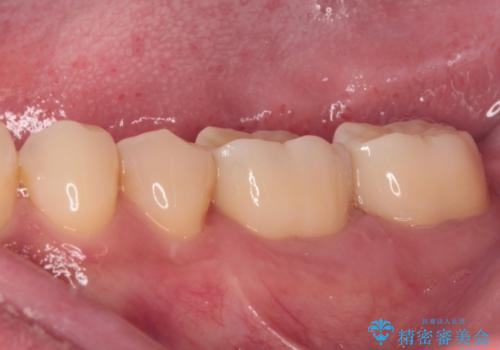

まずは仮歯に置き換え、歯周ポケットを除去するための外科処置(歯肉弁根尖側移動術)を行い、治癒を待ってセラミッククラウンにて補綴治療を行うこととしました。

外科処置後は知覚過敏症状が酷くなることが多いのですが、術後は比較的落ち着いており、スムーズに処置を進めることができました。